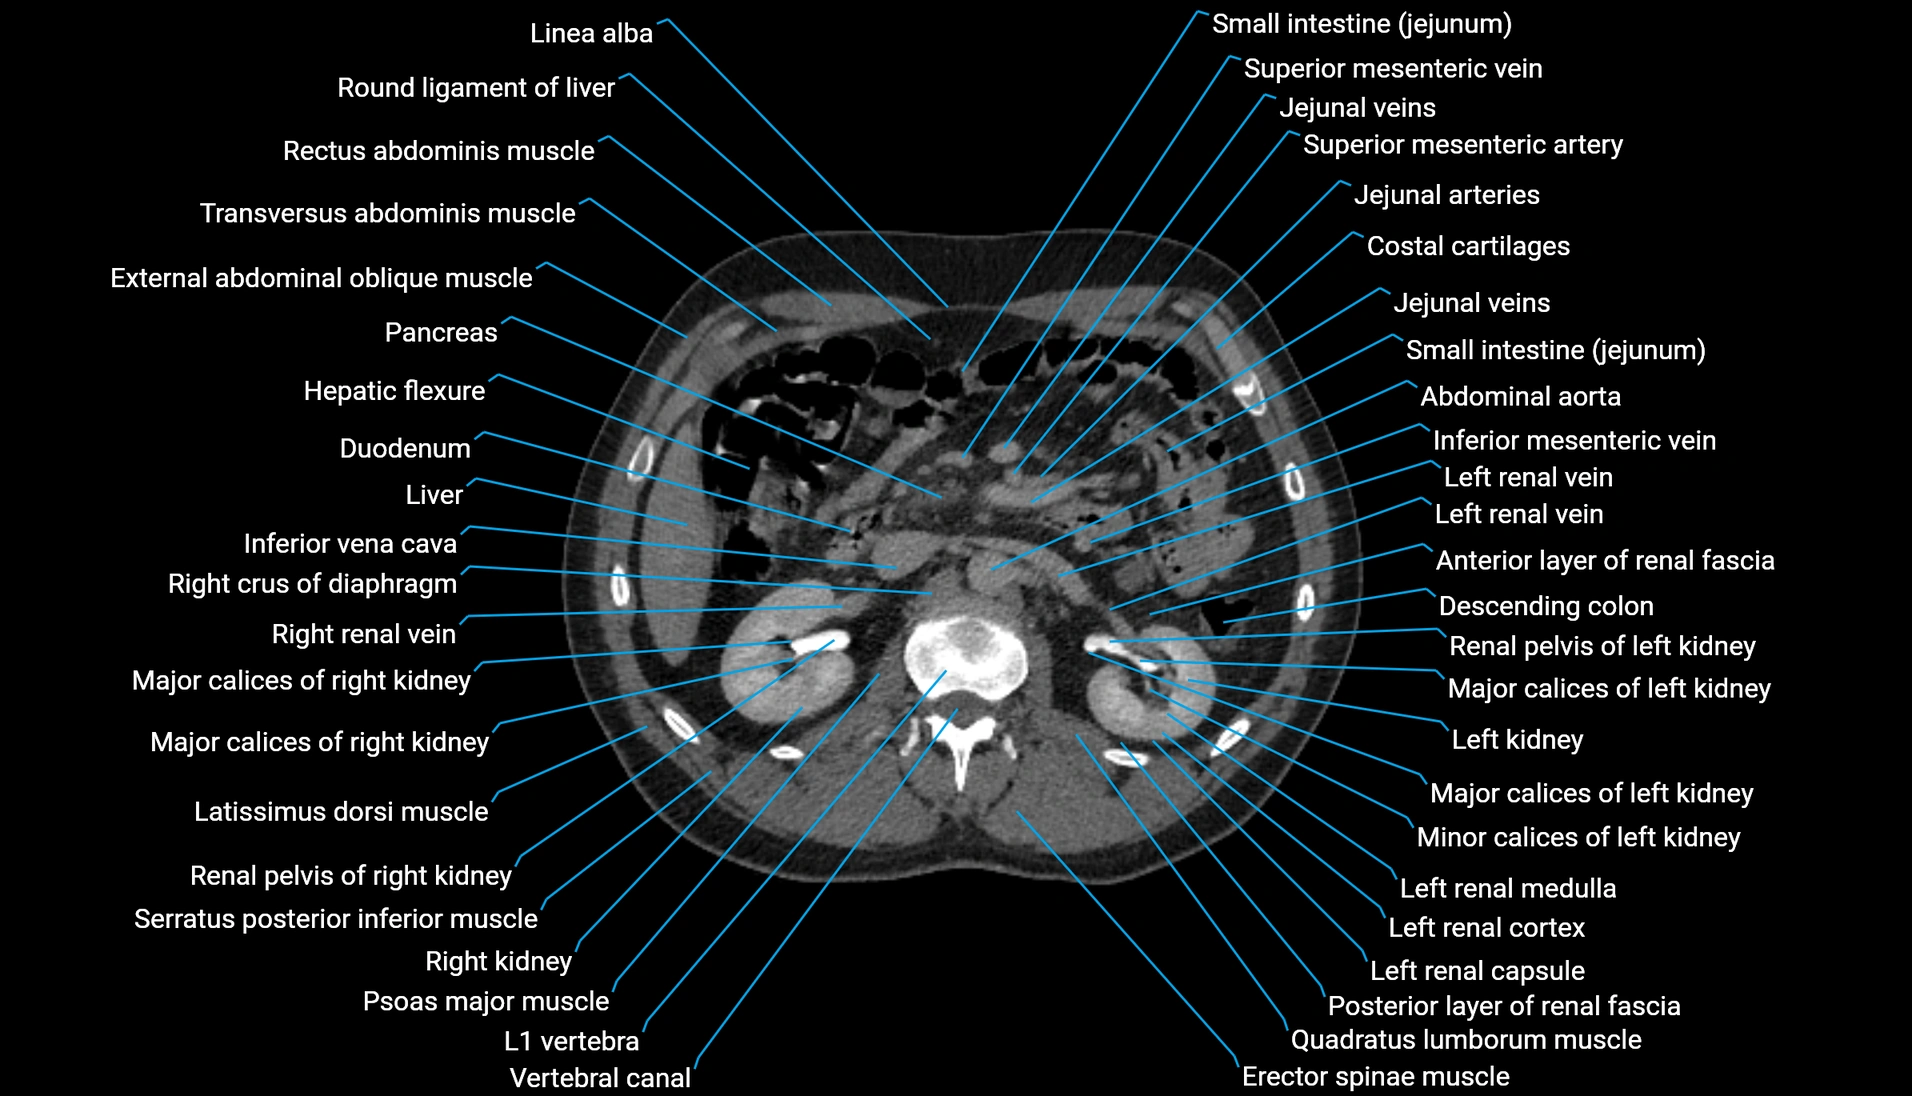

CT Appearance

Non-contrast CT:

-

Demonstrates cortical bone of acetabular rim in excellent detail

Detects fractures, dysplasia, retroversion, or bony overcoverage (pincer impingement)

3D reconstructions used in preoperative hip surgery planning

CT image